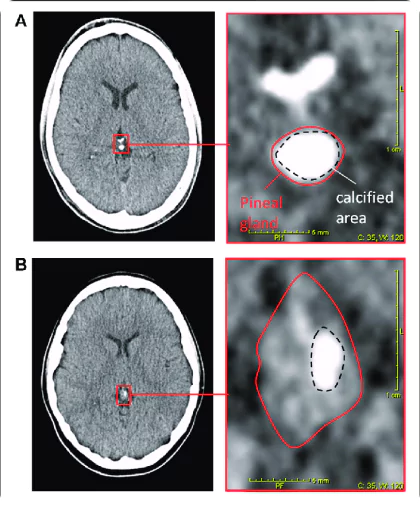

They found out that each one of these patients had a significant calcification1 in a tiny organ in the brain called the pineal gland.

Here’s how it starts to look: